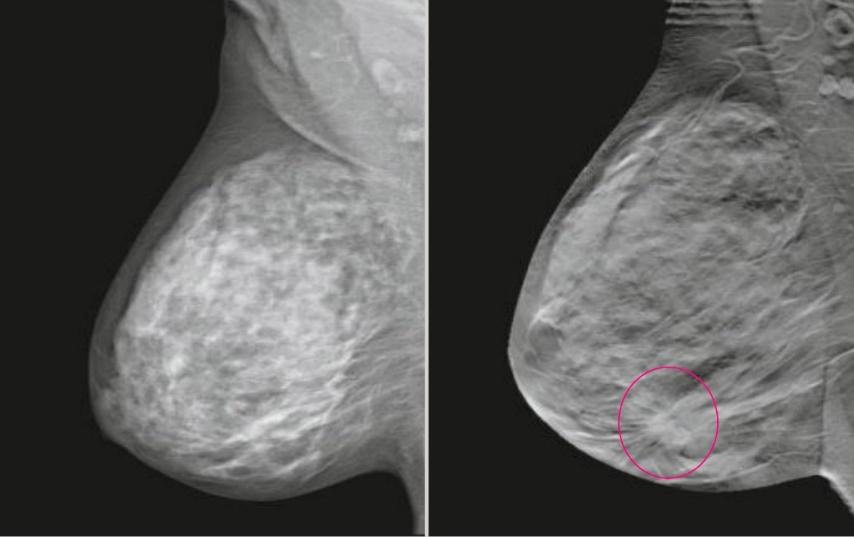

Шаг 9. Нужна ли функция контрастной спектральной двуэнергетической маммографии (CESM)?